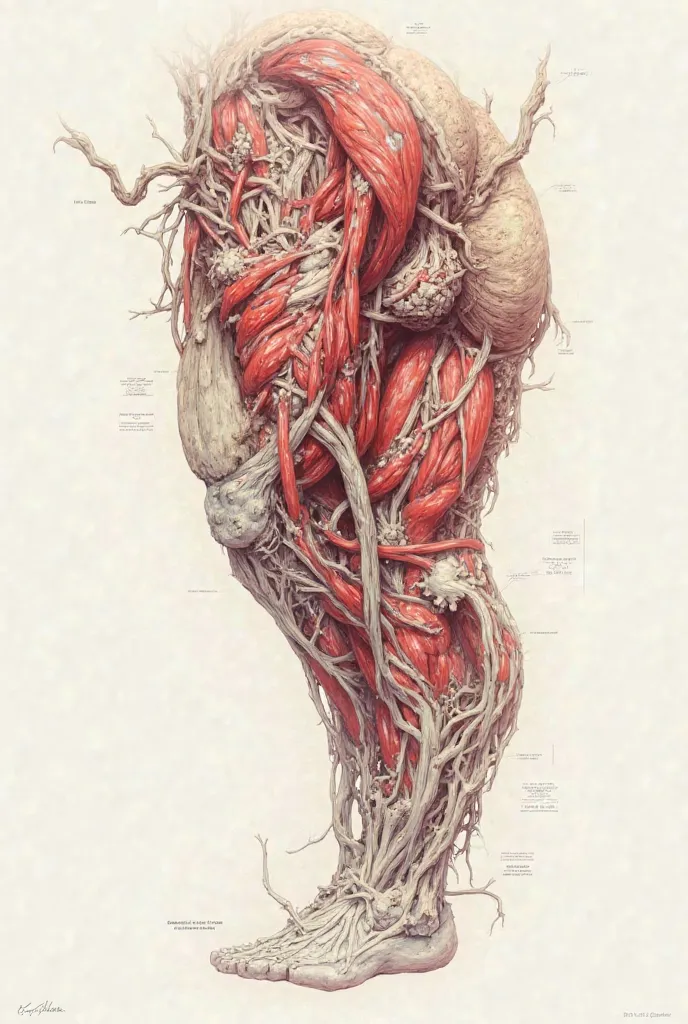

Dense irregular connective tissue, an image that I can use as a pattern so I can

dense irregular connective tissue, an image that I can use as a pattern so I can trace it, as if it were the sketch.

dense irregular connective tissue

an image that I can use as a pattern so I can trace it

as if it were the sketch